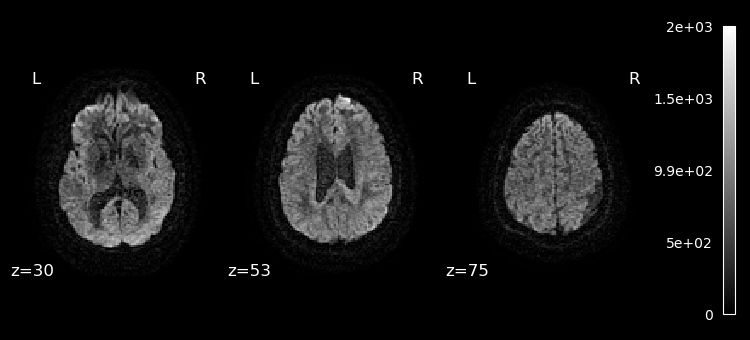

Lets plot the first 10 volumes.

%matplotlib inline

from nilearn import image

from nilearn.plotting import plot_epi

selected_volumes = image.index_img(dwi, slice(0, 10))

for img in image.iter_img(selected_volumes):

plot_epi(img, display_mode="z", cut_coords=(30, 53, 75), cmap="gray")